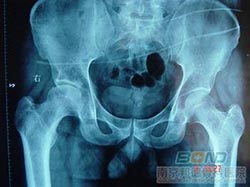

微创治疗股骨头坏死

我院专家介绍:对于股骨头坏死患者来说,选择治疗方法的标准无非就是高效、微创,这样的治疗方法才是患者一种理想的选择。那么,在目前众多股骨头坏死的治疗方法中,有这样的疗法吗?下面我们专家为大家介绍。

股骨头坏死治疗方法DSA介入疗法有着巨大的优势,具体如下: